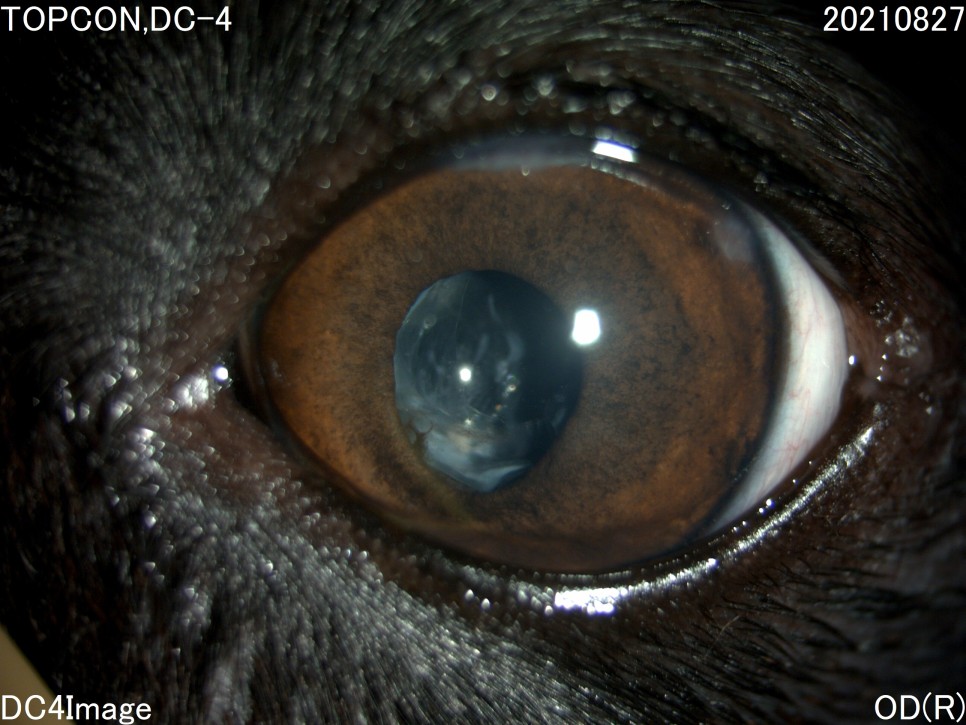

- 세극등 현미경 검사

양안의 백내장이 심하게 진행되고 있었지만 다행히도 당뇨병 관리를 하고 있는 전주 24시 동물병원은 당뇨병 관리 뿐만 아니라 눈 관리도 계속해 주셨기 때문에 내원 당시에는 양안 모두 심한 포도막염은 없었습니다.

그러나 왼쪽 눈은 백내장 단계 중 4기인 과성숙 단계로 진행되었으며, 이전에 앓고 있던 심한 포도막염에 의해 홍채의 일부가 수정체에 유착되어 있는 것이 보였습니다.

백내장이 오래 되거나 염증 반응이 심한 경우는 수정체를 감싸는 낭포 섬유화가 일어나 낭 자체에 백내장 파편이 붙어 있을 수 있는데, 자녀분이 바로 그런 상태였습니다.이런 경우 수술이 어려울 뿐만 아니라 수술 후 합병증의 발생률도 더욱 높아질 수 있습니다.